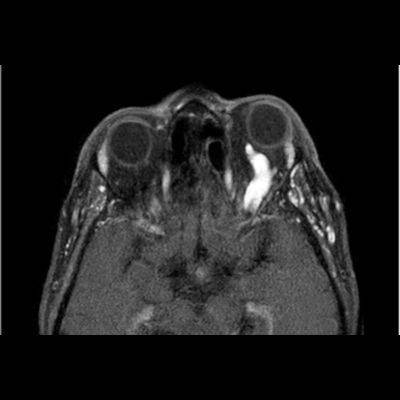

- B) Pre ve post-kontrast yağ basklılı T1A görüntüler incelendiğinde superior oftalmik venin (oklar) kontrast madde verildikten sonra homojen dolum gösterdiği, dilate ve tortiyoze görünümde olduğu izleniyor.

- BT ve MRG: Propitozis, ekstraokuler kaslarda genişleme, superior oftalmik vende genişleme ve tortiyozite, ipsilateral kavernöz sinüste genişleme gösterilebilir. Serebral venöz konjesyonu olan ve intrakraniyal basınçları yükselen hastalarda serebral ödem, hemoraji, leptomeningeal ve kortikal venlerin dilastasyonunu görülebilir. Bunlara ek olarak travmaya sekonder olgularda BT ile eşlik eden fraktürler gösterilebilir.